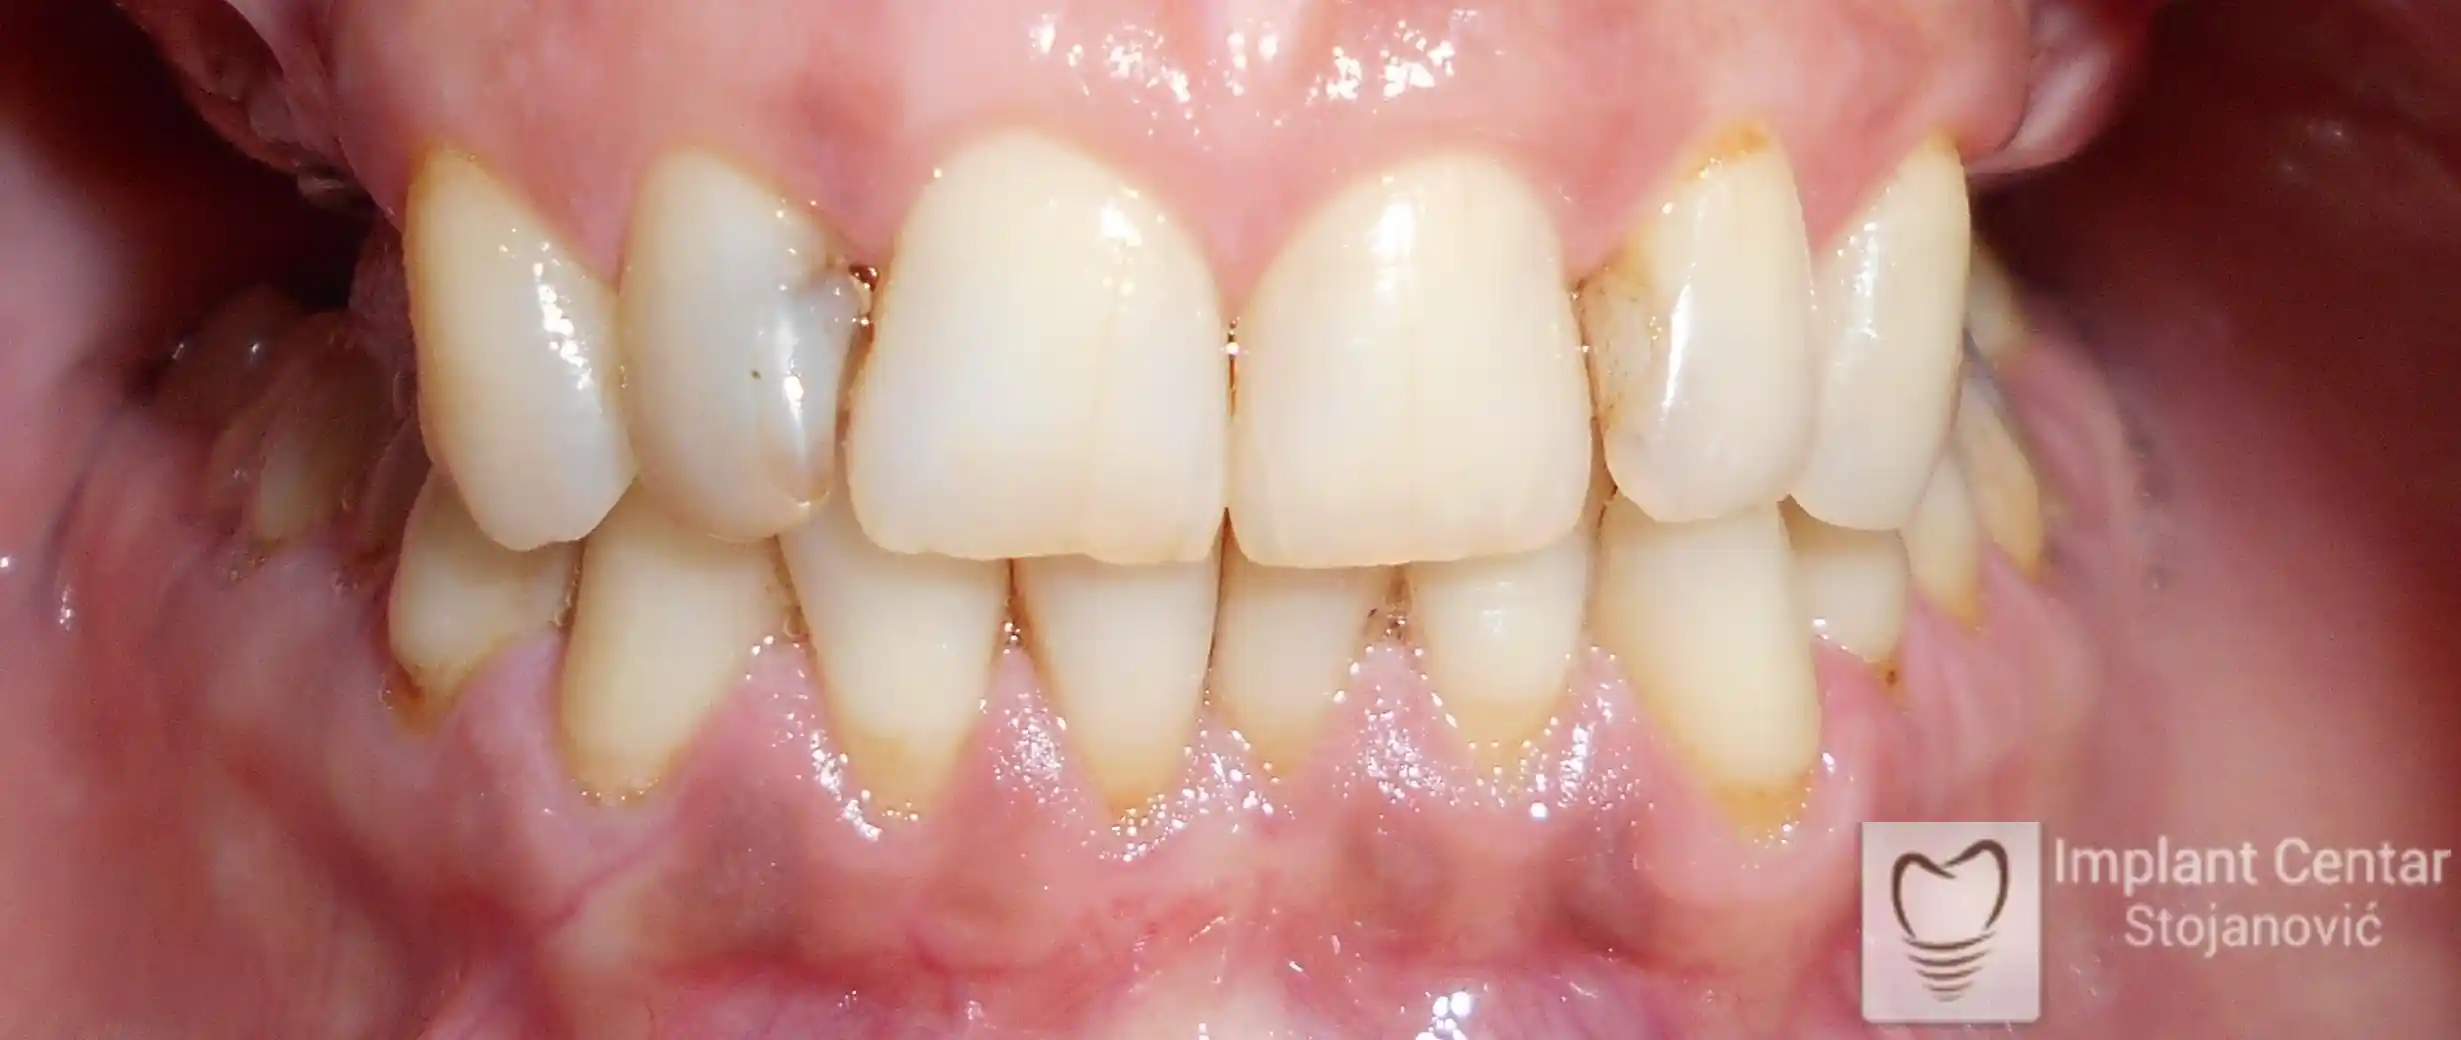

Nakon završetka perioda integracije implantata, izrađeni su cirkonijum-keramički mostovi u gornjoj i donjoj vilici (slika 6.).

Pacijent ističe da je prezadovoljan rezultatom — po prvi put nakon dugo vremena može normalno da žvaće i grize hranu, uz prirodan izgled novog osmeha.